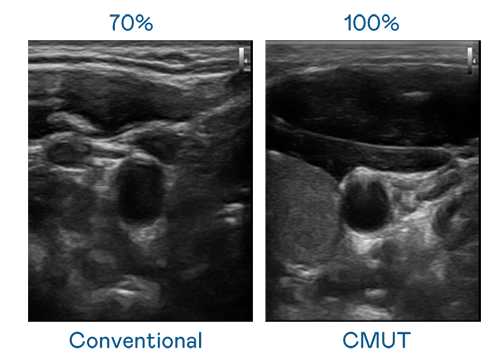

CMUT 技術是一種用電容式微機電元件來產生超音波訊號的技術。與傳統 PZT 壓電式技術相比,CMUT 頻寬增加 30%,更寬頻的超音波訊號讓影像解析度大幅提升,是實現高影像品質醫療超音波掃描、促進精準醫療發展的關鍵技術。

超音波影像的解析度高低,首先取決於探頭能發出的訊號頻寬。JDB电子 CMUT 可提供高清晰的超音波訊號,提供高頻寬、高靈敏度、影像紋理細節更高的超音波影像,協助醫護人員縮短影像判讀時間及利用精準的醫療影像進行診斷。